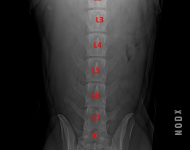

(5) typ 3 páteř VD

páteř VD

typ 1 I

typ 1 II